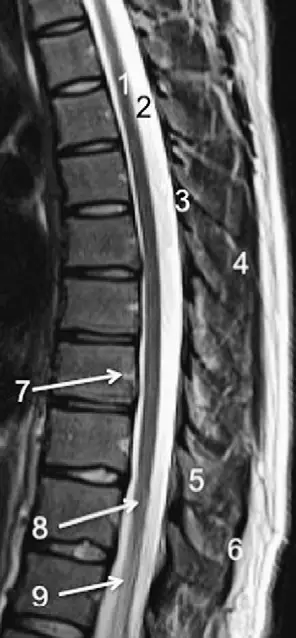

3,硬膜外脂肪;4,黄韧带;5,多裂肌;6,棘突;7,硬膜外静脉;8,棘上韧带图

硬膜外腔;ligamentum flavum 黄韧带;interspinous ligament 棘间韧带